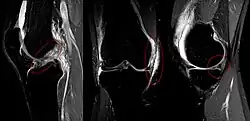

The unhappy triad, also known as a blown knee among other names, is an injury to the anterior cruciate ligament, medial collateral ligament, and meniscus. Analysis during the 1990s indicated that this 'classic' O'Donoghue triad is actually an unusual clinical entity among athletes with knee injuries. Some authors mistakenly believe that in this type of injury, "combined anterior cruciate and medial collateral ligament (ACL- MCL) disruptions that were incurred during athletic endeavors" always present with concomitant medial meniscus injury. However, the 1990 analysis showed that lateral meniscus tears are more common than medial meniscus tears in conjunction with sprains of the ACL.[1]